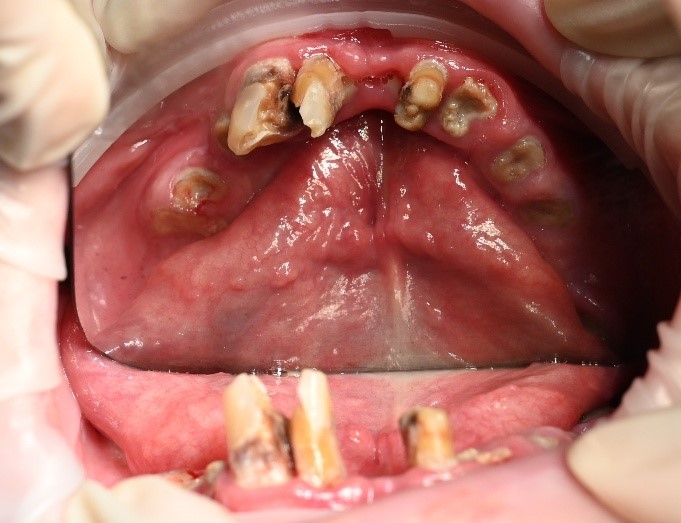

We completed a full clinical examination and took detailed records, including:

• clinical photographs

• intraoral photos

• OPG x-ray

• CBCT scan

• digital implant planning records

These records helped us carefully assess bone levels, gum health, and implant positions.

xAlthough the patient had moderate bone loss in some areas and signs of old chronic abscesses, his overall bone quality was still suitable for implants. There was no active pus or severe infection at the time of treatment.

We also discussed smile design and tooth shade with the patient so that the final result would feel natural and suit his face.